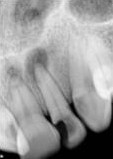

antes depois